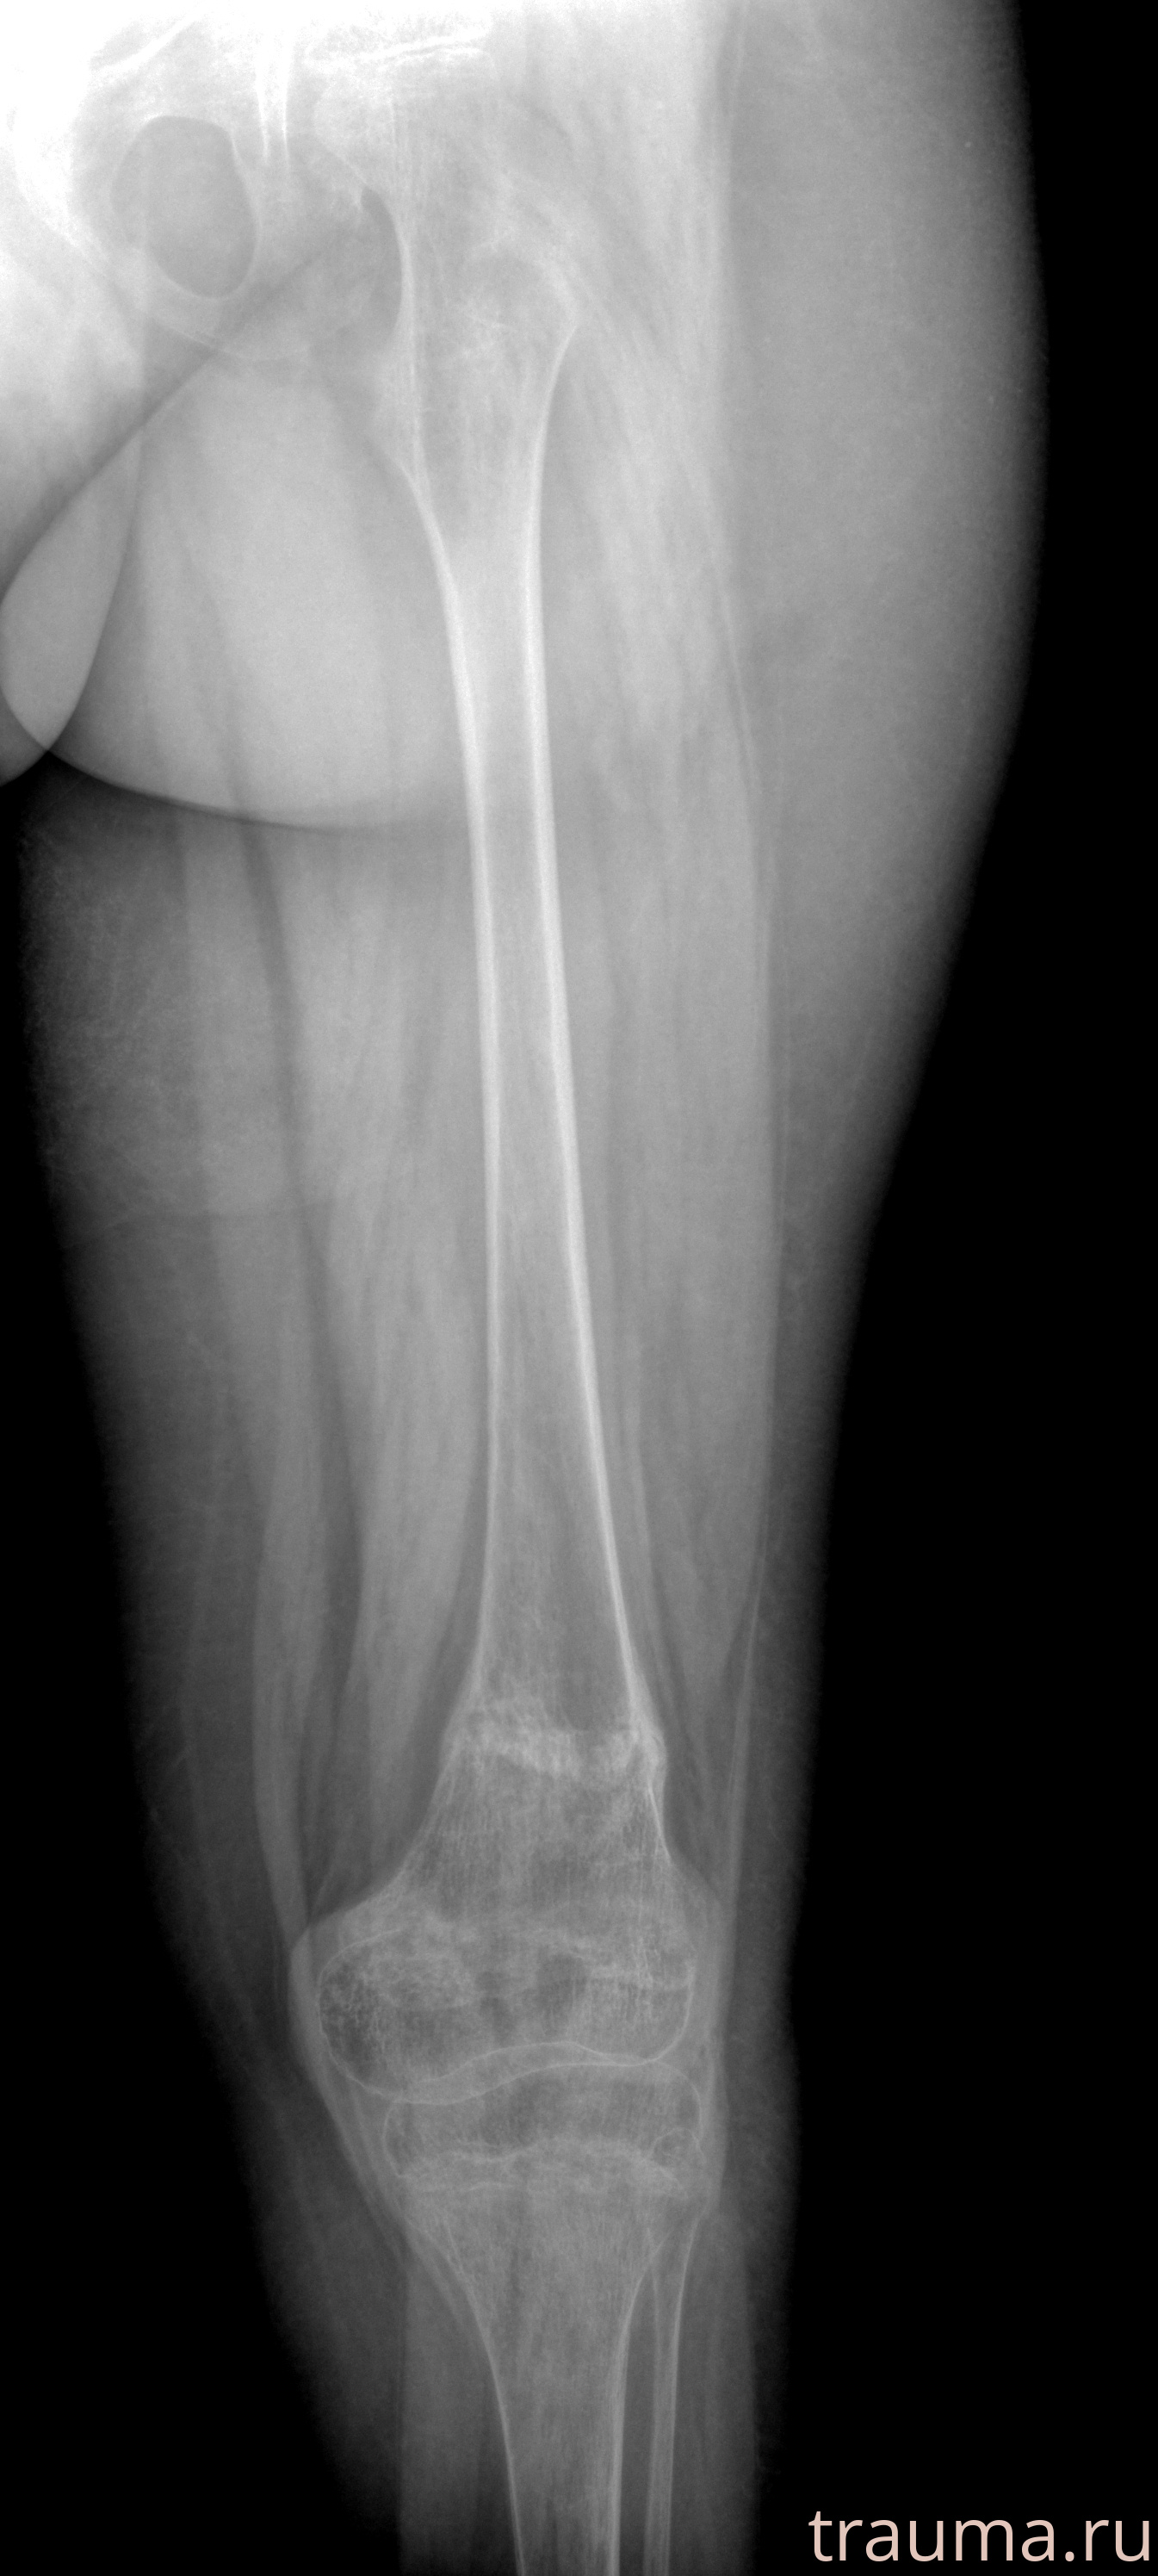

Рентген на дому: по вашему адресу приезжает врач-рентгенолог, травматолог-ортопед с мобильным рентгеновским аппаратом, проводит диагностику травмы или заболевания, делает необходимые рентгенограммы, дает рекомендации по дальнейшему лечению. Получить качественные снимки в домашних условиях возможно благодаря уникальной методике, разработанной МосРентген Центром для института  Склифосовского